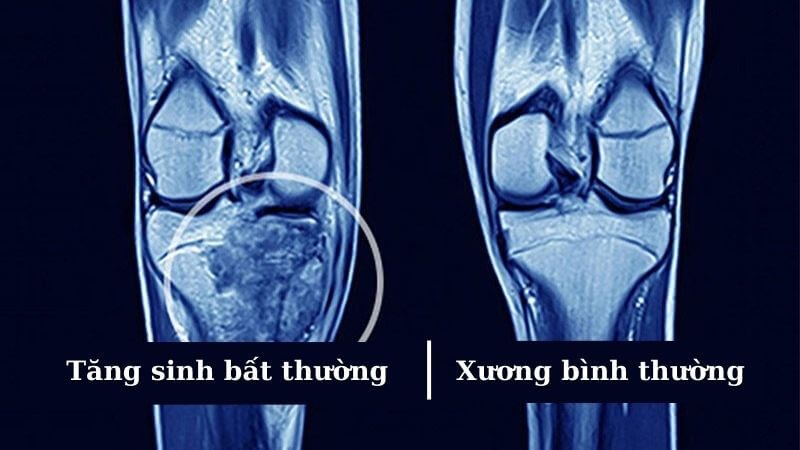

Ung thư xương là căn bệnh tăng sinh không kiểm soát các tế bào tạo xương, tạo sụn hoặc các mô liên kết của xương. Ung thư xương là một căn bệnh ít gặp nhưng khả năng di căn cao gấp 3-4 lần các loại ung thư khác.

Ung thư xương là các khối u ác tính có nguồn gốc từ các cấu trúc của xương